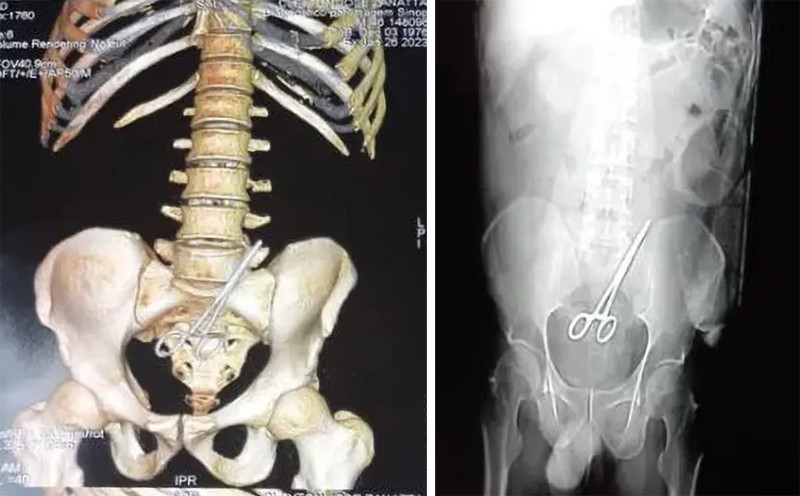

Theo New York Post, kết quả chụp CT ghi nhận, trong bụng của ông Zanatta có một chiếc kéo. Báo cáo cho biết các bác sĩ đã để quên dụng cụ cắt chỉ bên trong người bệnh nhân khi khâu vết thương cho ông. Sau đó, ê-kíp phẫu thuật lấy chiếc kéo ra khỏi bụng của ông Zanatta. Người bệnh đã bình phục sau sự cố y tế và đang trong tình trạng ổn định.